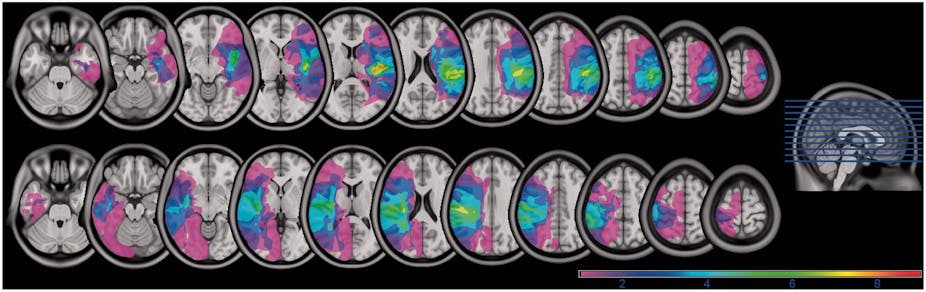

Our current understanding of Parkinson’s disease owes a large debt to brain scanning research. The TransEuro project is a current research program involving 15 institutions across Europe to investigate the use of stem-cell treatments in Parkinson’s. Positron Emission Tomography (PET) and Magnetic Resonance Imaging (MRI) form a cornerstone of the research in this project, as well as in many others. Brain scans are also often used clinically to rule out alternative diagnoses in cases of suspected Parkinson’s.

Until recently, it was unknown whether these patients were truly unconscious, or whether they had some awareness of their surroundings and just could not respond. Starting in 2006, Owen and his colleagues have shown that some of these patients are able to respond meaningfully, proving that they are indeed aware of their environment. They achieved this by using functional brain scans to measure brain activity in patients as questions were asked. One patient has even learned to change his brain activity in such a way that he is able to answer “yes” or “no” to questions.

Most other mental problems are unfortunately not nearly so clear-cut as Parkinson’s, or (fortunately) so extreme as a vegetative state. Describing the underlying brain problem in, say, autism, depression, or schizophrenia is more difficult, and our understanding of these disorders is therefore less advanced. It seems likely that these issues are probably associated with more subtle problems, across several brain regions. Some may even be undetectable with current technology, however that is a practical issue and will hopefully be resolved as the technology improves. Just because we can’t currently visualise all the brain effects associated with these disorders doesn’t mean they don’t exist.